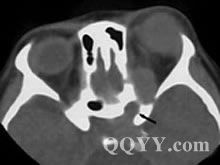

X線檢查所見,內型呈半圓形充盈缺損,邊緣整齊,有時其中央可見臍樣的潰瘍龕影;外型表現為受壓,壁黏膜完整,皺襞有拉平現象。檢查可見黏膜下腫塊的特徵,如有潰瘍時,從該處取活檢較易確診。